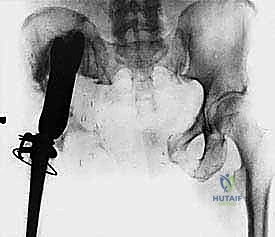

- Plain Radiography (FIG 2): While of limited value for early lesions, it provides an initial overview. As you can see in Figure 2A, we have a large lytic lesion of the right periacetabular region. Figure 2C shows a cartilage-forming lesion in the left ilium. However, plain films often underestimate the true extent of these tumors.

* CT with Intravenous Contrast and 3D Reconstruction (FIG 3): This is our workhorse for assessing bone involvement, destruction, and the critical relationship between the tumor and major pelvic blood vessels. It reveals any distortion of the pelvic anatomy and guides resectability. Figure 3A clearly shows extensive bone destruction and tumor extension into the pelvis and gluteal region. Figure 3C highlights an extensive tumor on the medial aspect of the ilium with destruction of the inner table.